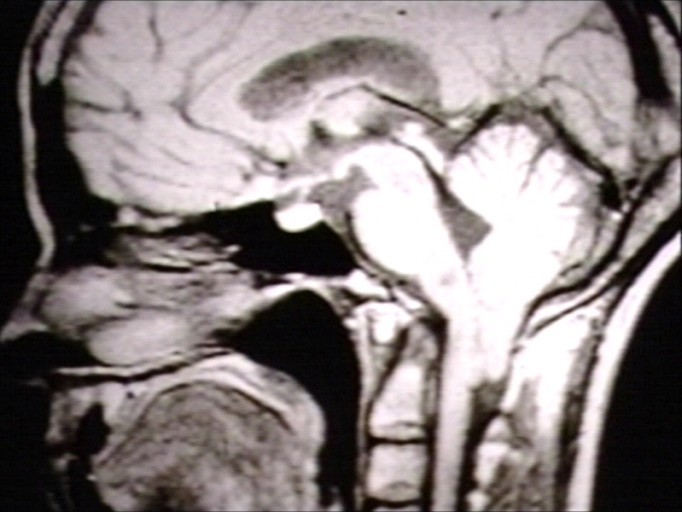

Патология Арнольда-Киари и сирингомиелия: медицинские схемы и фото